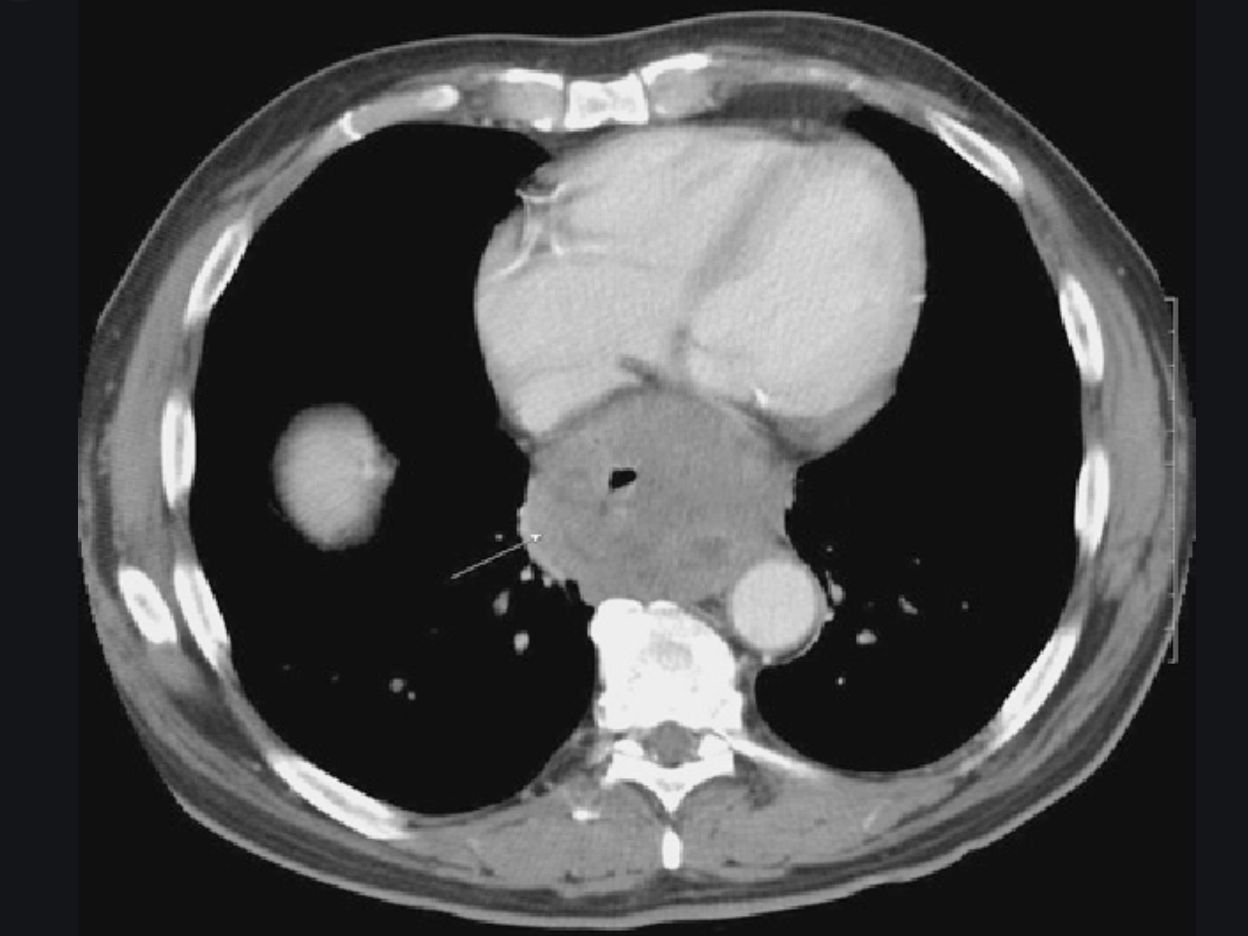

causes?

Anatomy of this condition

- Causes

- anticoagulant tx

- femoral catheterisation

- trauma

- Appearance

- high-attenuation fluid collection

- first several days +/- fluid level (hc level)

- if there is no further bleeding the high-density RBCs decompose to reduced density fluid

- fluid-fluid level

- Anatomy

- usually confined to the rectus muscle

- About 2cm below the umbilicus (arcuate line), the posterior posterior portion of the rectus sheath disappears and fibers of all three lateral muscle groups (External oblique, internal oblique, and transversus abdominis) passes anterior to the rectus muscle.

- This arrangement has imaging significance in that rectus sheath hematomas above the line are confined within the rectus sheath

- Inferior to the arcuate line, they are directly opposed to the transversal fascia and can dissect across the midline or laterally into the flank (as seen in pic 2)